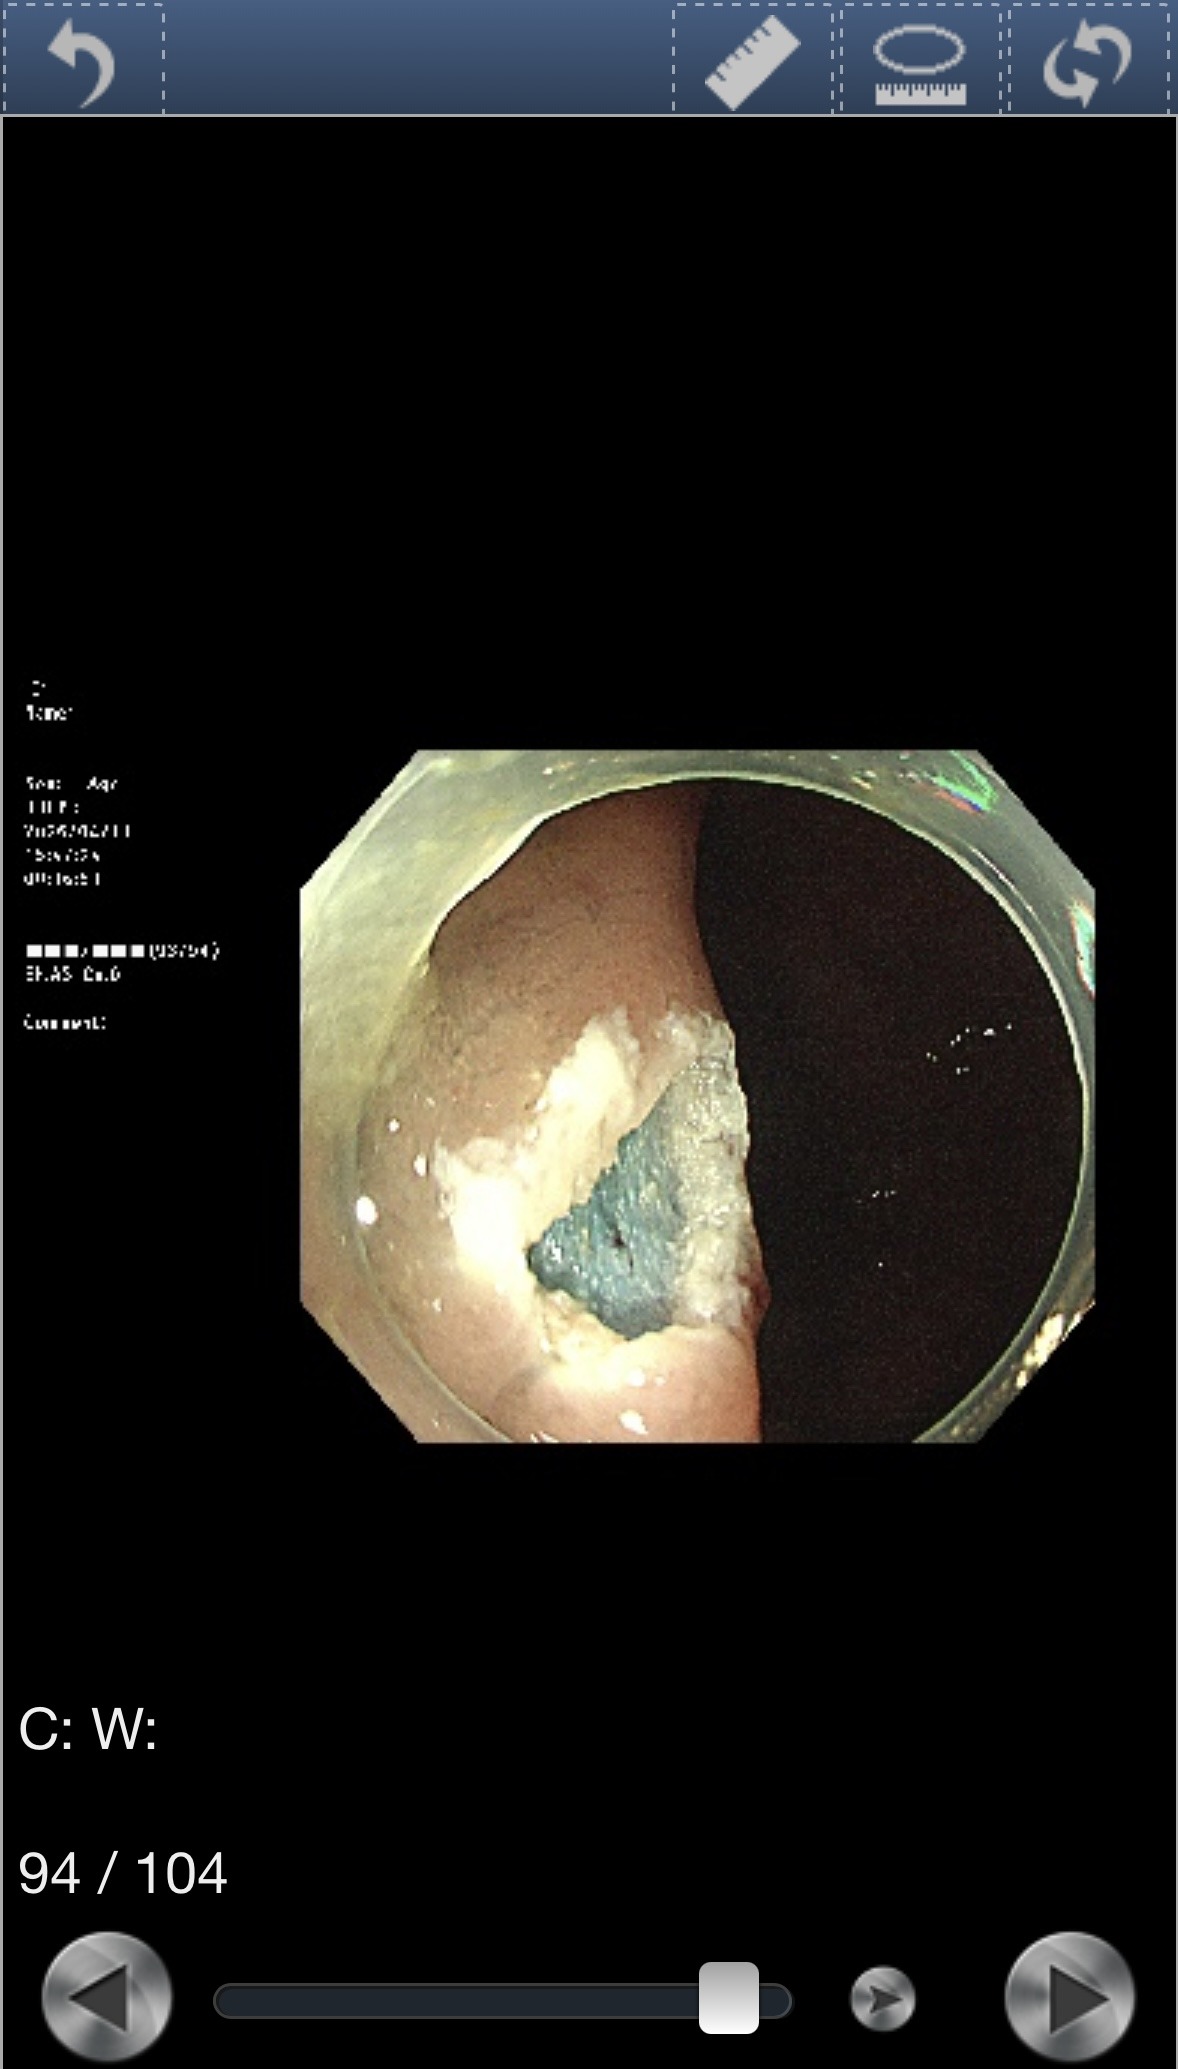

12mmポリープ発見・その場で切除

検査中にポリープが見つかった。サイズは12mm。

より精密に観察するため、色素を散布して輪郭を鮮明にした。

ドクターは「おそらく良性だと思います」と言ったが、念のため病理検査に出すため、その場で切除することになった。

切除後の粘膜はこうなる。